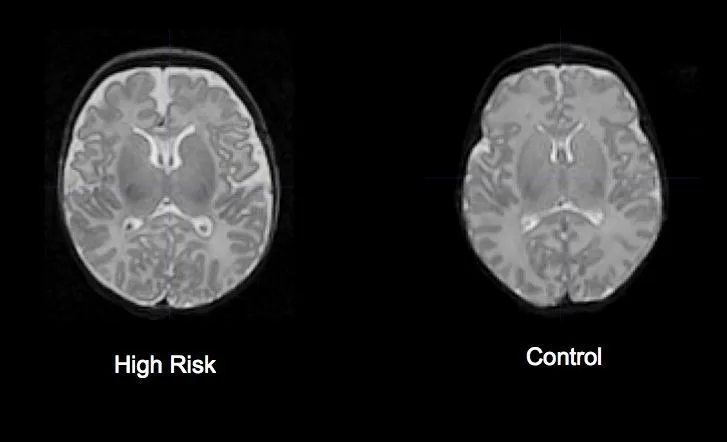

ADHD: Jak obrazowanie mózgu potwierdza neurobiologiczne podłoże zaburzenia?

Mniejsza objętość kluczowych struktur: Które obszary mózgu rozwijają się inaczej?

Badania strukturalne MRI u osób z ADHD konsekwentnie wykazują pewne różnice w objętości kluczowych struktur mózgu w porównaniu do osób bez tego zaburzenia. Obserwuje się mniejszą objętość całkowitą mózgu, a także specyficzne zmniejszenie objętości w rejonach takich jak:

Te zmiany korelują z typowymi objawami ADHD, takimi jak problemy z koncentracją, impulsywność i nadruchliwość, potwierdzając neurobiologiczne podłoże tego zaburzenia. Ważne jest, aby pamiętać, że są to różnice statystyczne, a nie absolutne markery diagnostyczne.

Opóźnione dojrzewanie kory przedczołowej a problemy z koncentracją i impulsywnością

Czy obraz MRI u dziecka z ADHD różni się od obrazu osoby dorosłej?

Tak, istnieją pewne różnice rozwojowe w wynikach MRI dla ADHD między dziećmi a dorosłymi, co dodatkowo wzmacnia ideę opóźnionego dojrzewania. U dzieci z ADHD różnice w objętości struktur mózgu są zazwyczaj bardziej wyraźne. Wraz z wiekiem, w procesie dojrzewania, mózg osób z ADHD może częściowo "dogonić" rozwój mózgu rówieśników, co jest zgodne z obserwacją, że u wielu osób objawy ADHD mogą się łagodzić w dorosłości. Jednakże, nawet u dorosłych z ADHD, subtelne różnice w strukturze i funkcjonowaniu mózgu mogą nadal być widoczne. Te obserwacje podkreślają dynamiczny charakter rozwoju mózgu i wpływ ADHD na ten proces na różnych etapach życia.